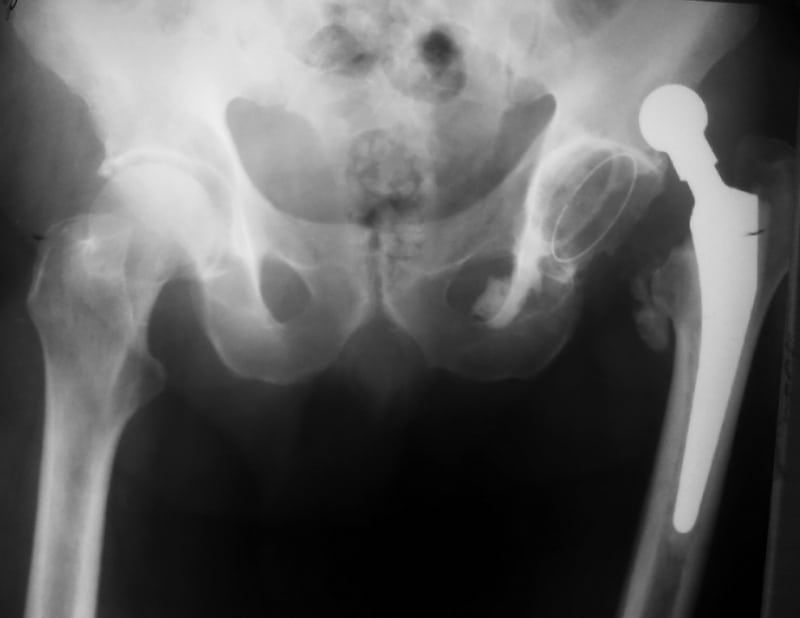

Kalça çıkığı tanısı, hastanın şikayetleri ve fiziksel muayene ile konulabilir. İlk olarak, doktor hastanın kalça bölgesini değerlendirir ve bacak hareketlerini kontrol eder. Eğer kalça çıkığından şüpheleniliyorsa, genellikle röntgen veya MR gibi görüntüleme yöntemlerine başvurulur. Bu testler, femurun asetabuluma nasıl oturduğunu ve eklemdeki olası hasarları net bir şekilde gösterir.

Özellikle doğuştan kalça çıkığı olan bebeklerde, doktorlar eklem başını asetabuluma manuel olarak geri yerleştirebilir. Bu işlem genellikle anestezi altında yapılır ve sonrasında eklem yerinde tutulur. Travmatik vakalarda ve ileri seviyedeki doğuştan kalça çıkıkları için cerrahi müdahale gerekebilir. Cerrahi müdahalede, kalça eklemi tekrar yerine yerleştirilir. Ardından bir metal plaka ve vidalarla sabitlenir.

Ayrıca, kalça eklemindeki yumuşak doku hasarları onarılabilir. Tedavi sürecinin ardından hastaların eklem hareketliliğini tekrar kazanabilmesi için fiziksel terapi önemlidir. Terapi, kasları güçlendirir ve eklemdeki sertliği giderir. Özellikle yaşlı hastalarda, kalça eklemi tamamen hasar görmüşse ve cerrahi tedaviyle düzeltilmesi mümkün olmuyorsa, kalça protezi takılabilir. Kalça protezleri, eklemdeki ağrıyı azaltır ve hareket kabiliyetini artırır.